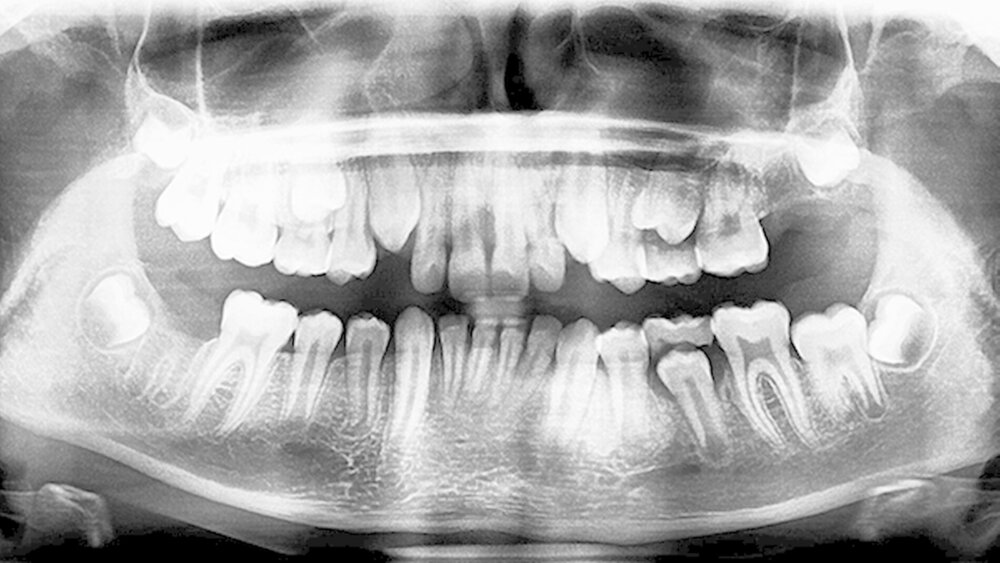

Der Patient und seine Mutter wurden ausführlich über die Behandlungsmöglichkeiten (Behandlung mit Lokalanästhesie, in ITN oder unterstützend mittels Sedierung und Lokalanästhesie) aufgeklärt. Die Zähne 27 und 47 wurden am 23. Juli 2015 im Mund-Kiefer-Gesichts-Zentrum Frankfurt in Sedierung und mit lokaler Betäubung operativ entfernt. Die Operation verlief komplikationslos und die Wunden heilten nach Nahtentfernung vollständig ab. Am 30. Juli wurde im Rahmen der Nachkontrolle ein postoperatives OPG angefertigt (Abbildung 3).

Postoperativ wurden die Zähne in bukko-lingualer Richtung mittels einer diamantbelegten Trennscheibe geteilt. Visuell zeigte sich nun ein großer Hohlraum im koronalen Dentinbereich, sowohl an Zahn 27 als auch an Zahn 47. Die histologische Untersuchung der Zahnfragmente ergab für beide Zähne: Zahnanlagengewebe mit akuter Entzündung (Abbildungen 4 bis 6). Der Patient befindet sich seitdem im regelmäßigen Abstand von sechs Monaten in einem prophylaktischen Recall. Die Abbildung 7 zeigt das postoperative Zahnschema vom 19. August 2015

In unserem Fall zeigte sich röntgenologisch sowohl für Zahn 27 als auch für Zahn 47 eine weitaus größere Zerstörung - auch im pulpanahen Bereich. Nach sorgfältiger Abwägung und Einbeziehung der Wünsche von Eltern und Patienten wurde sich in interkollegialer Abstimmung zwischen MKG, KFO und Kinderzahnärztinnen für eine Extraktion der beiden Zähne und eine spätere kieferorthopädische Einordnung der Weisheitszähne entschieden. Weitere Röntgenaufnahmen und ein DVT, wie von Ari empfohlen (2014), wurden nicht angefertigt.